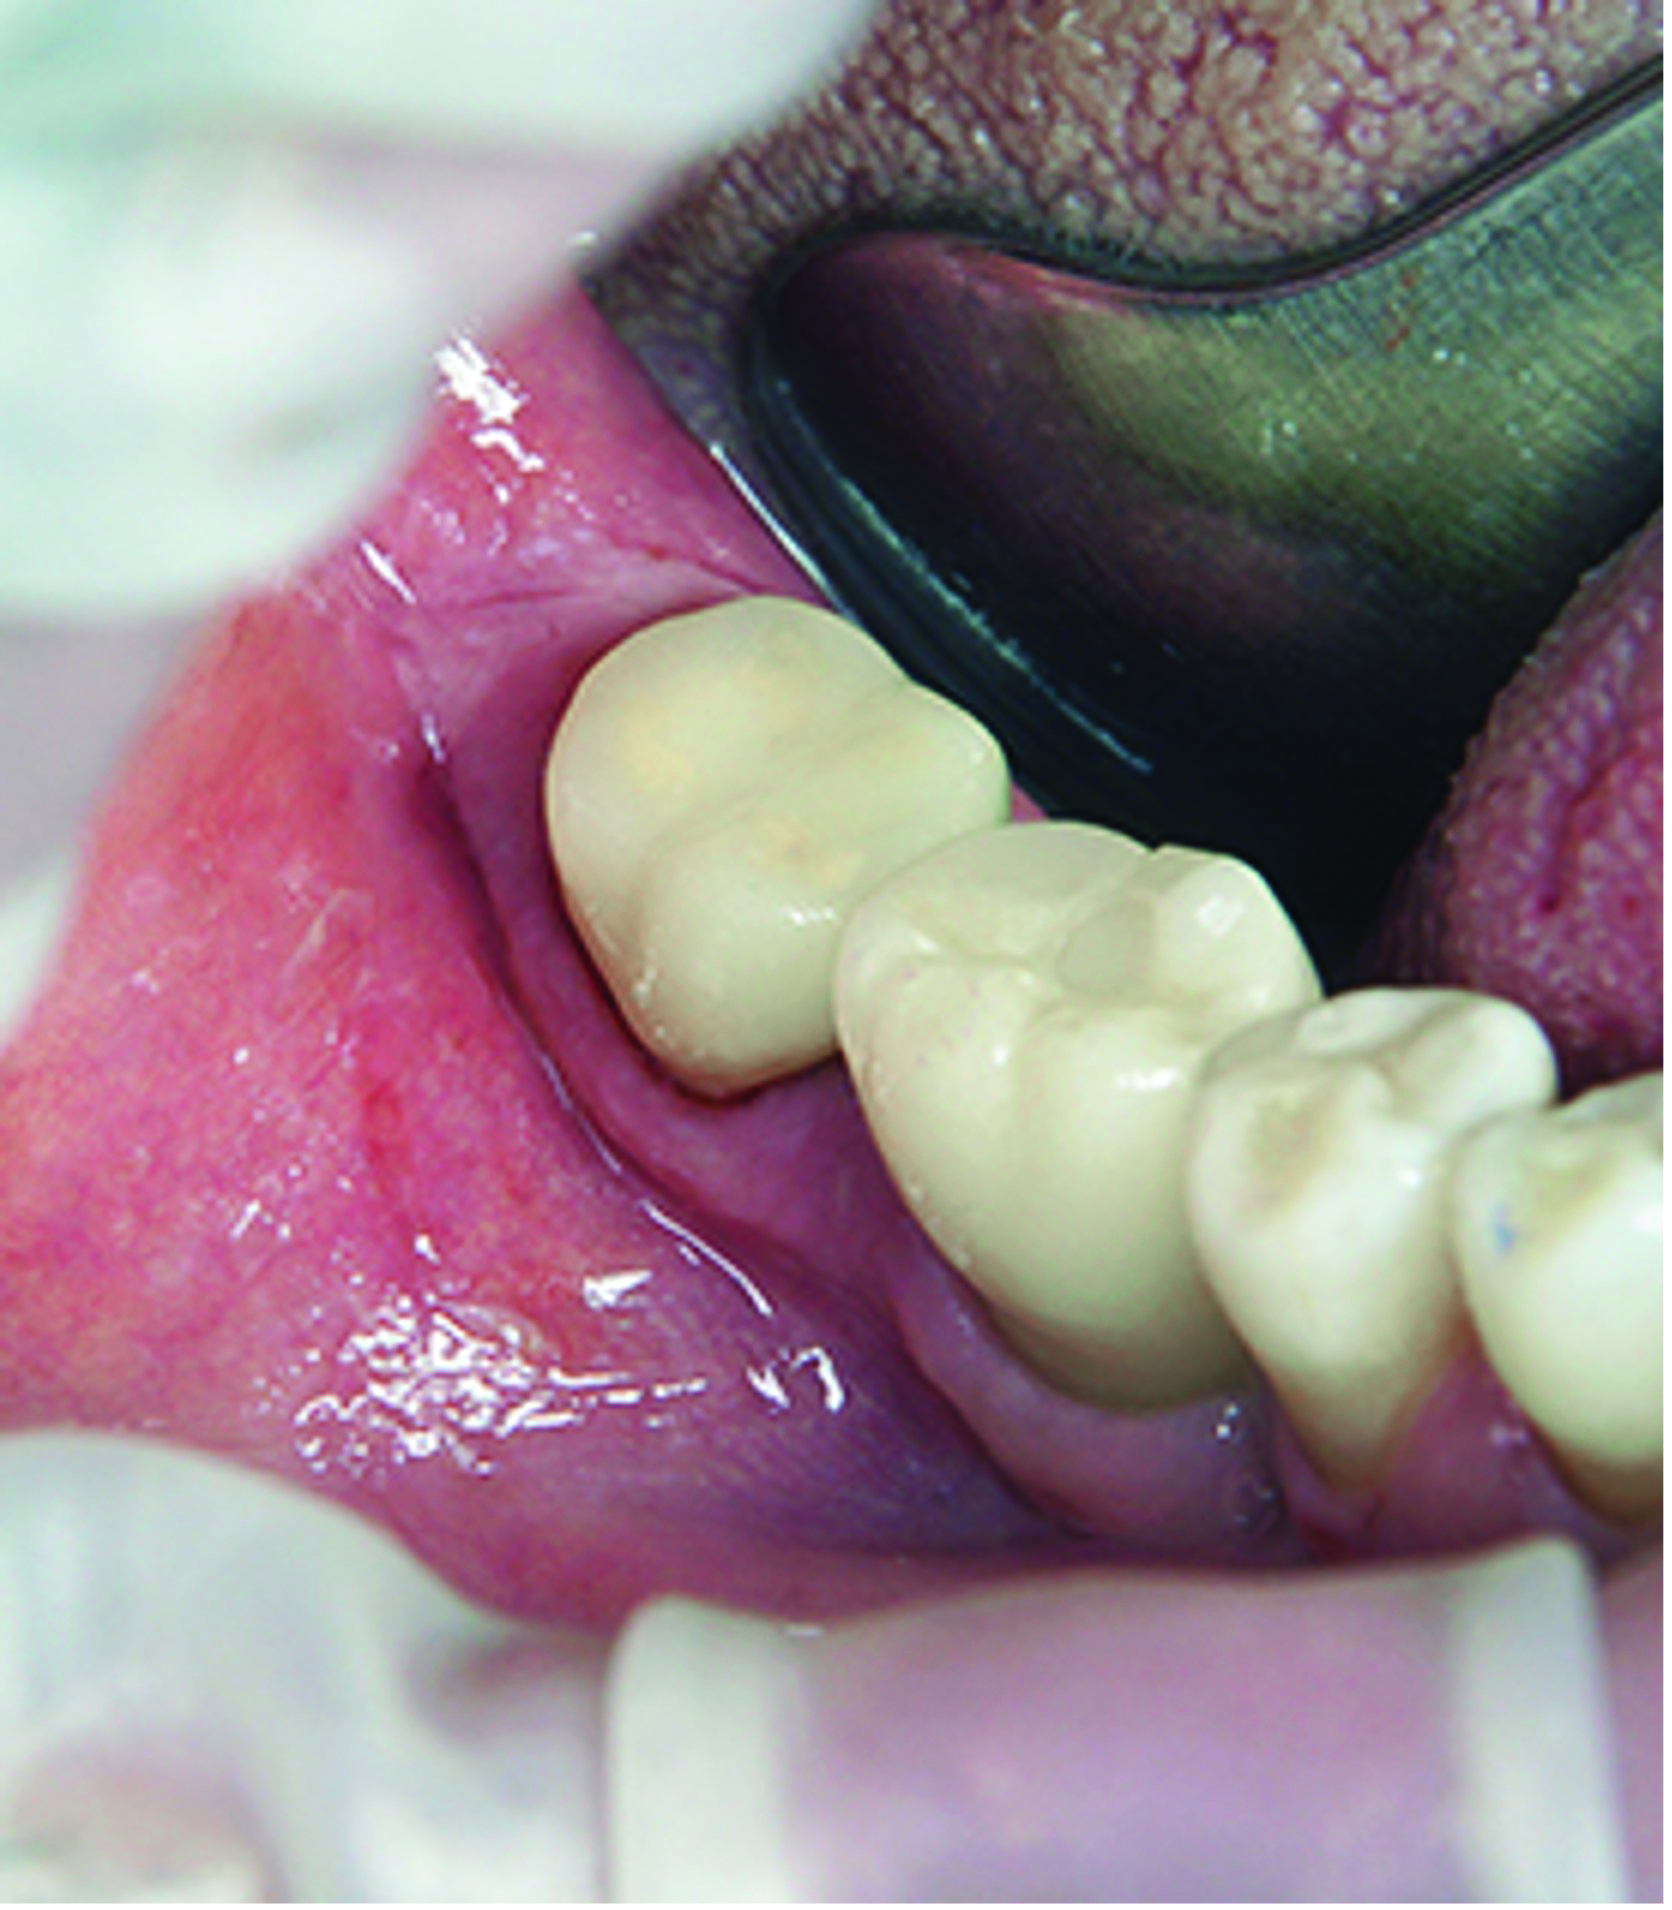

After removal of the rubber dam, final polishing was performed to ensure smooth margins and improve the longevity of the ceramic restoration. This step was carefully executed under the DOM with a fine-grit diamond flame bur to efficiently remove any excess cement post-cementation without damaging the restoration or tooth structure (Figure 20). The gingival retraction cords were then removed under the DOM to prevent soft-tissue trauma, with care taken to ensure that no cords were left trapped in the sulcus.

The proximal contact was checked by gently passing dental floss through the contact point without it snapping, followed by lateral movement of the teeth to avoid dislodging the restoration. Articulating paper was then used to assess static and dynamic occlusion, with any high spots adjusted microscopically to prevent over-reduction. Microscopic verification of the occlusion helps ensure that the restoration aligns with the patient's bite and functions seamlessly with the natural dentition (Figure 21 and Figure 22).

Fig 20. After removal of the rubber dam, the restoration margin was carefully fine-polished all around the tooth under microscopic guidance.

Figure 20

Fig 21. Vestibular view of the treatment result.

Figure 21

Fig 22. Occlusal view of the treatment result.

Figure 22